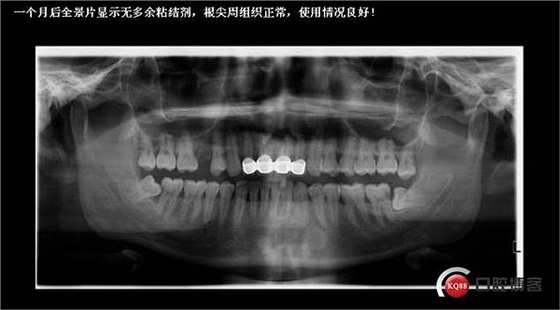

七診半個月后復診,口腔衛(wèi)生不錯,望保持!牙齦也很健康,期待更長遠的治療效果!